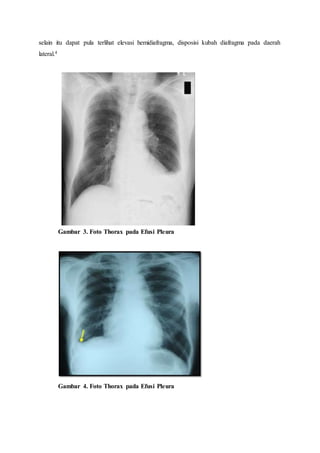

Pemeriksaan foto toraks posteroanterior (PA) dan lateral sampai saat ini masih

merupakan yang paling diperlukan untuk mengetahui adanya efusi pleura pada awal

diagnosa. Pada posisi tegak, akan terlihat akumulasi cairan yang menyebabkan hemitoraks

tampak lebih tinggi, kubah diafragma tampak lebih ke lateral, serta sudut kostofrenikus yang

menjadi tumpul. Untuk foto toraks PA setidaknya butuh 175-250 mL cairan yang terkumpul

sebelumnya agar dapat terlihat di foto toraks PA. Sementara foto toraks lateral dekubitus

dapat mendeteksi efusi pleura dalam jumlah yang lebih kecil yakni 5 mL. jika pada foto

lateral dekubitus ditemukan ketebalan efusi 1 cm maka jumlah cairan telah melebihi 200 cc,

ini merupakan kondisi yang memungkinkan untuk dilakukan torakosentesis. Namun pada

efusi loculated temuan diatas mungkin tidak dijumpai.

Pada posisi supine, efusi pleura yang sedang hingga masif dapat memperlihatkan

suatu peningkatan densitas yang homogen yang menyebar pada bagian bawah paru,

selain itu dapat pula terlihat elevasi hemidiafragma, disposisi kubah diafragma pada daerah

lateral.4

Gambar 3. Foto Thorax pada Efusi Pleura

Gambar 4. Foto Thorax pada Efusi Pleura